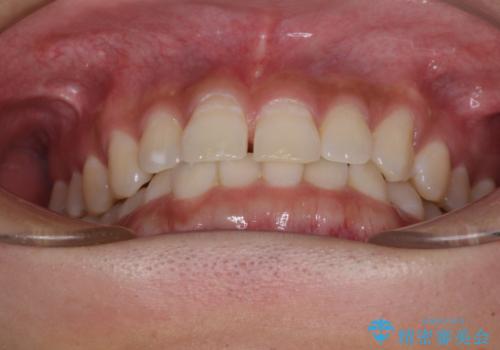

隙間の空いた前歯を治したい 上顎の部分矯正

- 上顎前歯の隙間を気にして来院された患者様です。

下顎前歯に叢生がありましたが、特に気にしていらっしゃいませんでした。

下顎臼歯にインプラント補綴治療がされており、全顎治療するにはクラウンの作り替えが必要となる旨を説明し、ワイヤー装置により上顎のみの矯正治療を行うこととしました。

下顎前歯の叢生解消も提案しましたが、上顎の隙間が閉じたことで満足されました。